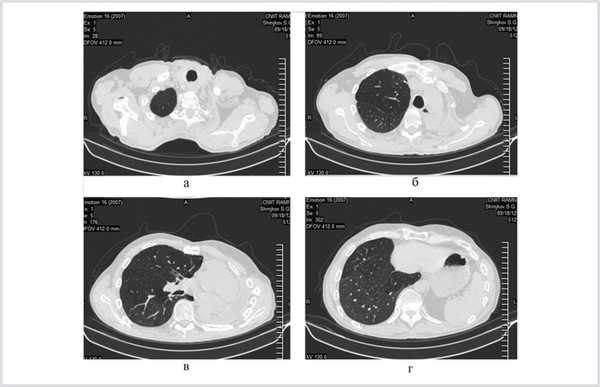

При контрольном обследовании 27.02.13 (через 1 год и 6 мес после последней операции) состояние больного удовлетворительное, обострений туберкулеза не было. При многократных исследованиях мокроты МБТ не найдено. При компьютерной томографии отмечены рассасывание и уплотнение очагов в единственном резецированном легком (рис. 4).

Рис. 4. Компьютерные томограммы больного Ш. через 1 год и 6 мес после завершения хирургического лечения.

Динамика функциональных показателей на этапах хирургического лечения и при выписке представлена в табл. 2.